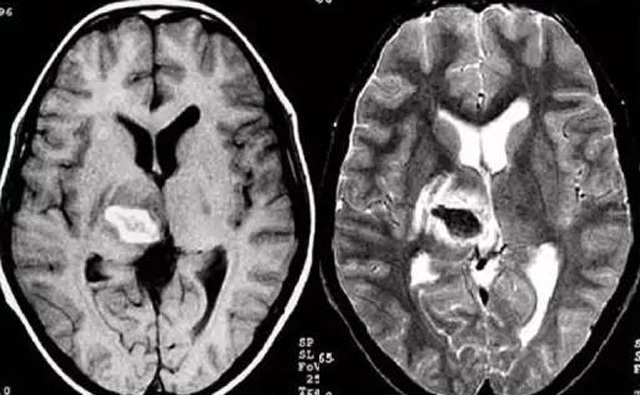

经颅多普勒超声(TCD)磁共振MRI检查脑出血诊断的作用是什么?

发现病人出血脑梗相关症状时候第一时间就医,需要携带以往的影像检查资料。向医生提供相关的病史基本资料。做影像检查时候需要全身不携带金属物品。检查时候身体保持不动,不然伪影对检查结果有干扰。磁共振MRI发现缺血性卒中后,帮助进一步查找病因。由于CT上小脑跟脑干颅骨影响,容易导致漏诊。MRI检查可以对CT检查不足的补充。短暂的脑缺血TIA也需要进行影像检查。短暂性缺血一般10几分钟后好转。检查目的可以确定TIA的病因。降低脑梗死的发生率。磁共振有助于排出TIA表现的颅内病变,有诊断及时治疗的价值。磁共振MRI检查时间比较长,不太适合急诊病人。但是可以发现脑干小脑的出血问题。因为急性脑梗死的早期和急性期,缺血区的脑组织还没有完全坏死,头颅CT不能显示病灶,所以就需要MRI磁共振检查,这个对陈旧跟亚急性出血显示比较好。缺点性价比不高,费用比较贵。头颅的磁共振MRI在发病后的几天CT的敏感降低时候发挥大作用。,MRI可作为诊断蛛网膜下腔出血和了解破裂动脉瘤部位的一种重要方法,必要时进一步进行DSA检查,帮助制订临床的手术治疗方案,